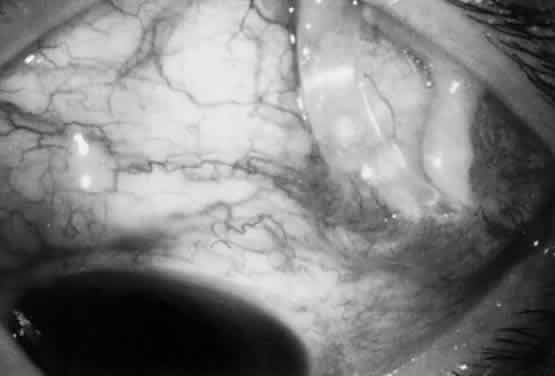

The filtration site is placed posteriorly near the equator in the latest generation of shunts. The morphologic features of these blebs are different from those of functional blebs at the limbus, as seen with a trabeculectomy. They are typically thick-walled, with prominent conjunctival vascularity, and are elevated over the reservoir (Fig. 1). Although the silicone tube and PMMA plates of the Molteno shunt are biologically inert and do not produce tissue necrosis, a thick fibrous capsule envelops the reservoir and tube (Fig. 2)25–29

Fig. 2. Histologic features of bleb surrounding a Molteno reservoir.

These histopathologic findings are similar to those reported for the Schocket tube,28 Baerveldt tube,29 and White pump shunt.24 The shunt apparatus is not degraded; it remains intact, with little or no adjacent inflammatory response and without fibrous adhesion to the implant. In contrast, a case report of an original Krupin valve composed of Supramid* describes significant biodegradation, with loss of tensile strength, attenuation, and fracture.30

The fibrous capsule that may originate from the episclera24 is relatively acellular and composed of scattered fibroblasts, collagen, and glycosaminoglycans.25,28 Aqueous is thought to pass through the fibrous capsule and into the orbital circulation through capillaries and lymphatics in addition to conjunctival circulation.25,28 Schocket used horseradish-peroxidase as a tracer and showed that aqueous could pass through the orbital vessels.28 In that study, the reservoirs preserved an area for bleb formation that had a relatively large surface area from which aqueous diffused. Orbital outflow, mechanical maintenance of a bleb zone, and a large surface area distinguish posterior tube shunts from limbal filtering operations and help to explain their success in the treatment of difficult cases of glaucoma.